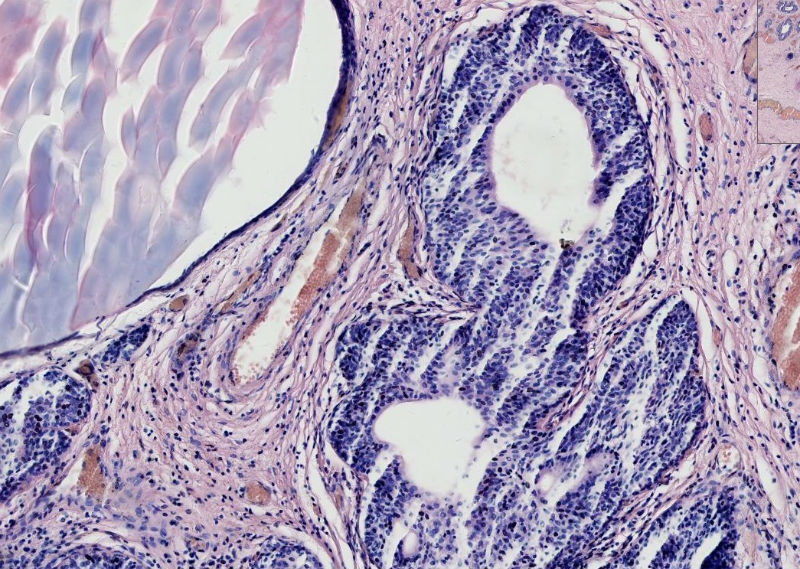

• 尿道外口肿物图2

图2

在传两个高倍

腺囊性尿道炎

上皮下间质中有淋巴细胞浸润,移行上皮巢团中央有柱状上皮围成的腺样腔隙。诊断:腺囊型尿道炎。

支持腺囊型尿道炎